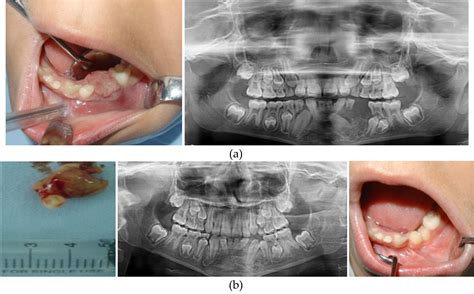

The diagnosis of a cancerous jaw tumor typically involves a combination of clinical examination, imaging studies, and biopsy. The diagnostic process may include:

• Clinical examination: A healthcare professional will examine the jaw and surrounding areas for any signs of swelling, tenderness, or abnormalities.

• Imaging studies: X-rays, CT scans, MRI, or PET scans may be used to visualize the tumor and determine its extent.

• Biopsy: A small sample of the tumor tissue is removed and examined under a microscope to confirm the presence of cancer cells.

In some cases, additional tests may be required to determine the stage of the cancer and whether it has spread to other parts of the body.

Treatment Options for Cancerous Jaw Tumors

The treatment of cancerous jaw tumors depends on several factors, including the type and stage of the cancer, the patient's overall health, and their preferences. Common treatment options include:

• Surgery: Surgical removal of the tumor is often the primary treatment for cancerous jaw tumors. The extent of the surgery will depend on the size and location of the tumor.